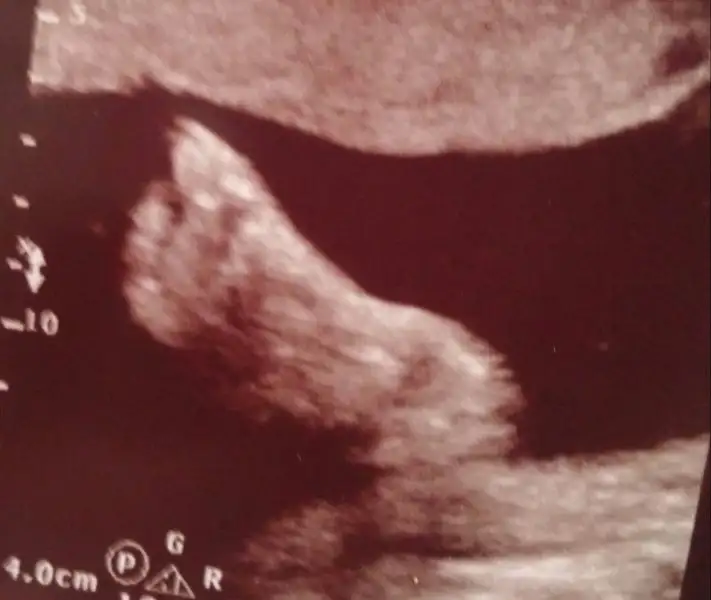

İçinden gelen bir resim ekle :)